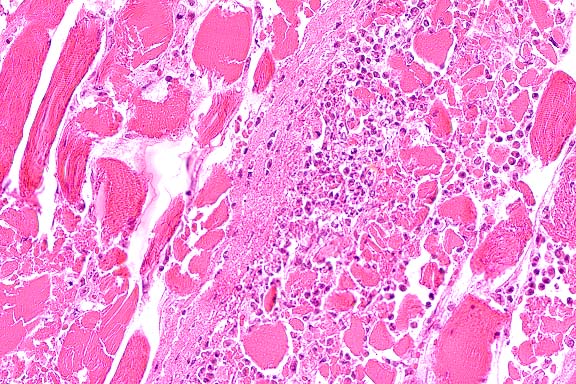

20x

obj

- Case 7-2. Skeletal muscle. Muscle fibers are

hyalinized, fragmented, and have a loss of cross striations,

and are infiltrated and separated by neutrophils, macrophages,

serocellular debris.

-

- AFIP Diagnoses:

- 1. Skeletal muscle: Degeneration and necrosis, diffuse, with

multifocal histiocytic and neutrophilic inflammation, quarter

horse, equine.

2. Skeletal muscle: Sarcocysts, few.